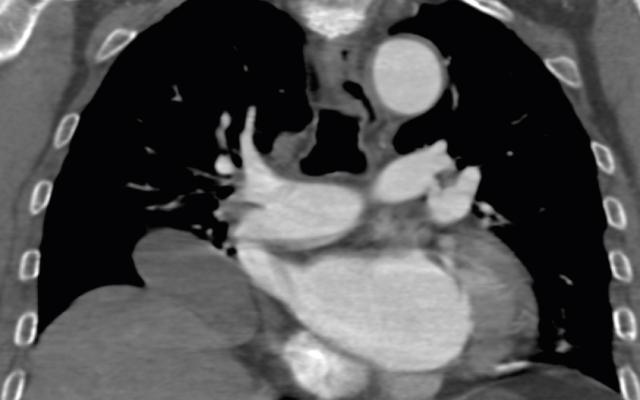

Een 80-jarige man, bekend met cognitieve stoornissen na ernstig hersenletsel, werd op de polikliniek Geriatrie gezien in verband met achteruitgang van de cognitie. Hij was enkele weken eerder op de SEH geweest in verband een influenza A-infectie. Op de longfoto waren toen infiltratieve afwijkingen gezien, maar ook een bolronde afwijking. Op de polikliniek had hij geen klachten meer van kortademigheid, slikstoornissen of hoesten. De bloeddruk (117/67 mmHg), polsfrequentie (83/min) en zuurstofsaturatie (100%) waren niet afwijkend. Ook verder lichamelijk onderzoek bracht geen afwijkingen aan het licht. Als verklaring voor de bolronde afwijking dacht de geriater aan een restafwijking na de…